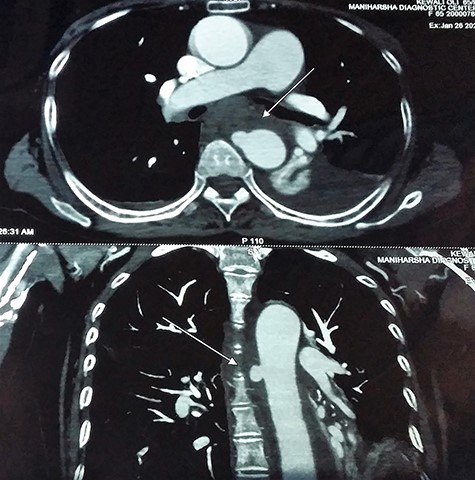

Ultrasound of abdomen and pelvis was normal. Upper gastrointestinal tract (UGI) endoscopy was done immediately, which revealed ulceration with a blood clot at 25 cm of the esophagus (Fig. 1).

UGI endoscopy, clot with underlying ulceration in the esophagus.